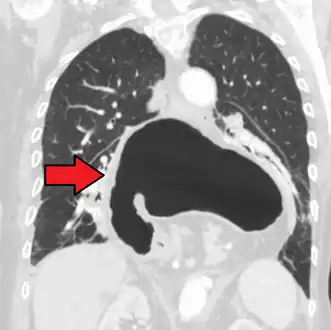

A hiatal hernia as seen on CT

A large hiatal hernia as seen on CT imaging

A large hiatal hernia as seen on CT imaging- As seen on ultrasound[9]